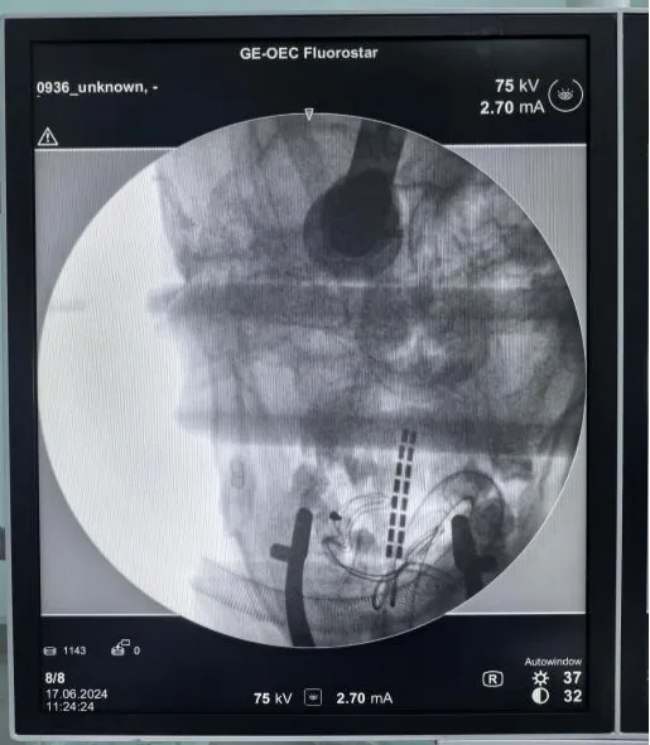

手术中

患者影像资料